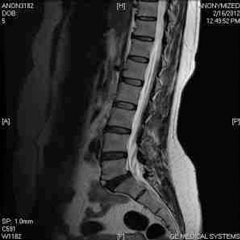

MRI

MRI is routinely used to evaluate soft tissue, spine, and joint injuries. We coordinate MRI scanning with affiliate imaging centers. When necessary, we can arrange for an MRI with contrast, open MRI imaging, and sedated MRI procedures. The physicians of OSIC work directly with a dedicated team of musculoskeletal radiologists to provide the most comprehensive evaluation and documentation of injury.